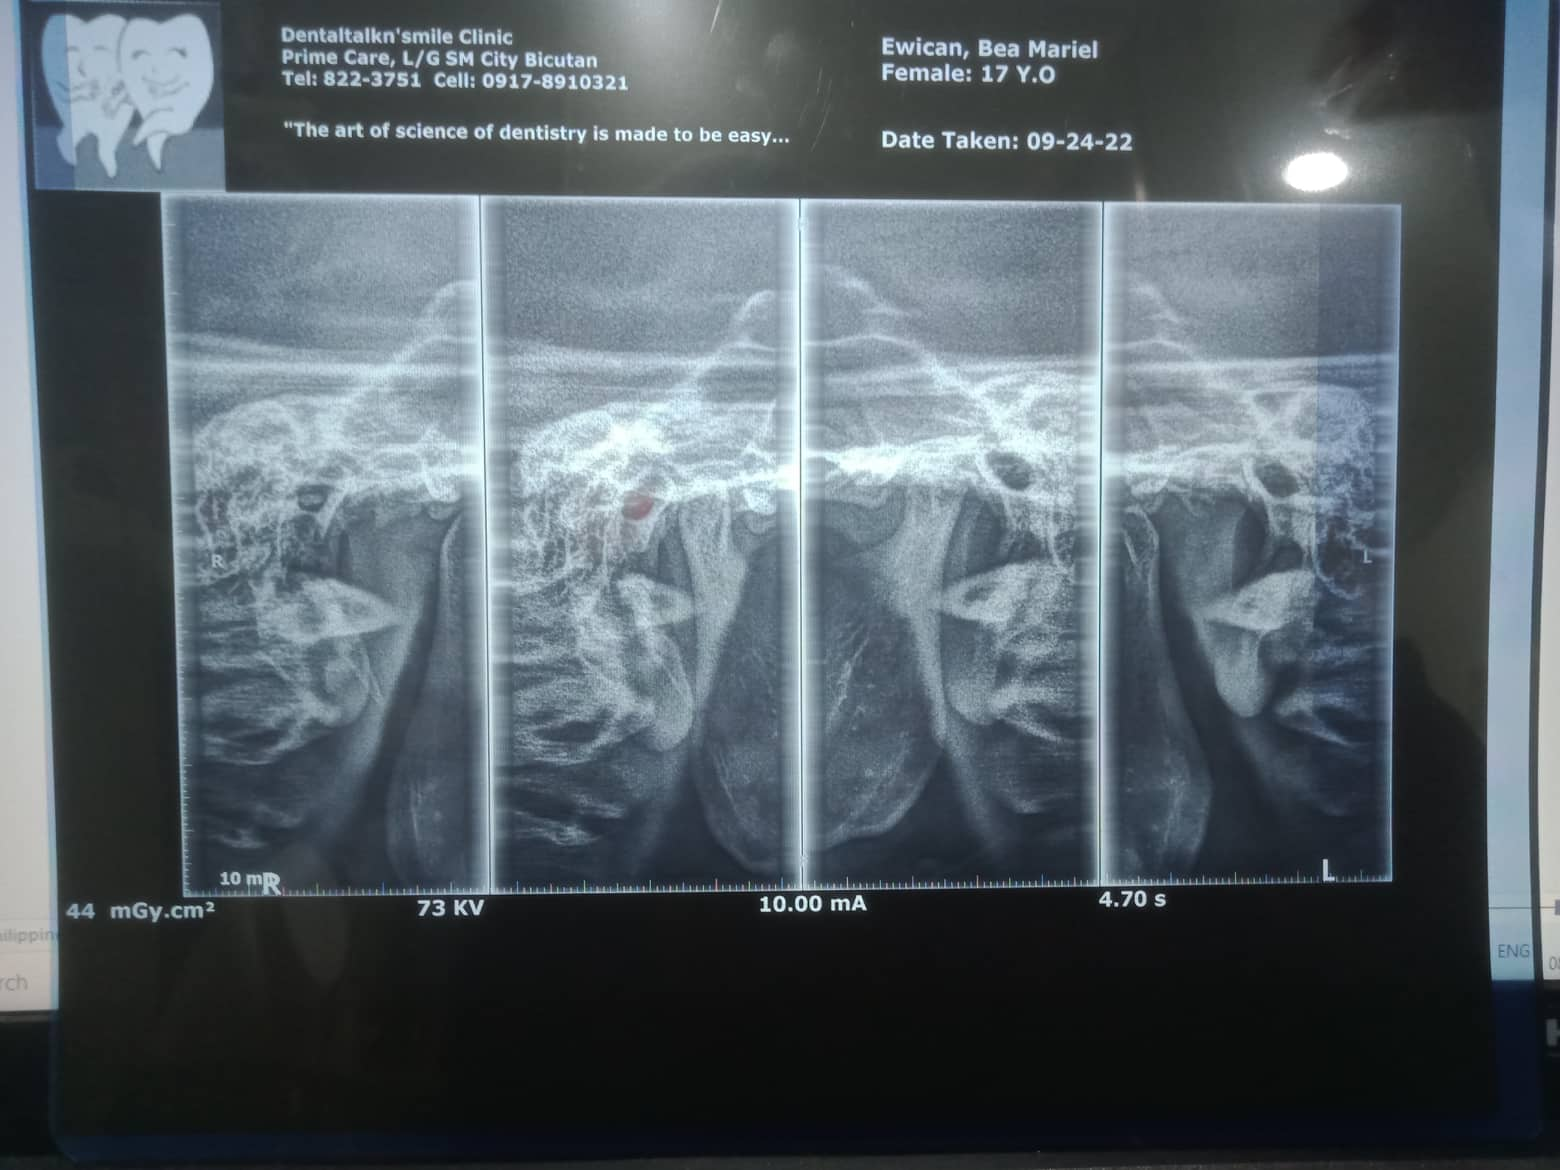

Edit Record Check our patient data records. Add patient information Patient Info Profile picture Last Name First Name Middle Name Birthdate Age Street Barangay City Country Zip Code Contact number Email Procedure 10/8/22- OP(L); RESTO #12 (MLABIAL), #11(MLINGUAL), #21(MLINGUAL) 1/21/23- Adj Same wire /23-UL same wire/reattached #15 04/1/23- Adj./Laser 07/01/23- 18niti upper/14 niti lower/laser- tmj pain relie 07/26/23- posterior splint reduction anterior 2mm posterior 3.5mm RX: procosa 08/12/23- 16SS L 18 NiTi U/ canine to canine Fox/ reduced splint to 0.5mm 09/20/23- 16ss UL 14- 16/ 24-26 chain 32 to 42 chain 10/18/23- closing space on lower Rw #42/ reduced height of splint same wire UL/ reattached #24 11/29/23-reattcahedment 24 reduced splint height box elastic anterior/ penguin same wire 01/05/24 ADJ same wire/ extrude 22/12 fox elastic extrusion 02/27/24 -same wire -reattachment #21,#41,#44 03/19/24 Adj 04/23/24 reattached #21 Adj 18 RC Niti-lower fox elastic(box) quadrant on posterior Occlusal pads on 46/37 installed same heights on the splint no more wearing of splint 06/11/24 ADJ same wire chain 12/22 reattached #42 08/30/24 adj class II elastic rabbit 5oz 12/21/24 class II elastic rabbit 3.5 oz chain U same wire next meeting close open bite reattached #33 01/30/25 Adj same wire reattached #33,42 box elastic penguin 04/01/25 Reattached #43, #42 Kobayashi wire #12,22 Class II elastic 5 oz. rabbit 06/13/25 same wire elastic chipmunk reattached #33 File 311406133_1205581633332847_2276520068966312254_n.jpg File 2 310788104_1189315538336441_931730254721665696_n.jpg File 3 bea_mariel_ewican.jpg File 4 bea_ewican.jpg File 5 File 6 File 7 File 8 File 9 File 10 File 11 File 12 File 13 File 14 File 15 File 16 File 17 File 18 File 19 File 20 Retain Record Retain Record Yes No Save Your Changes